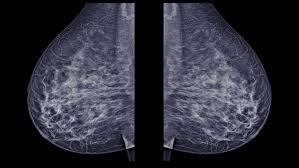

Most screening mammograms include two views of each breast taken from different angles. Abnormalities such as cancerous tumors usually appear brighter because they are denser. Any area that does not look like normal tissue is a possible cause for concern. However, 3d allows us to 'slice through' the breast, making thin sections, like on a ct scan. A diagnostic mammogram is used to check for breast cancer when there is a sign or symptom of disease. These deposits show up as tiny white spots on a mammogram, and there may be only one or two, or too many to count, says jay baker, md, a breast imaging specialist at the duke cancer center. 1 the gray areas correspond to normal fatty tissue, while the white areas are normal breast tissue with ducts and lobes. A 3d mammogram is used to look for breast cancer in people who have no signs or symptoms. Screening mammograms have been used since the 1980s. Dense breast tissue appears solid. Digital breast tomosynthesis (tomo), also known as 3d mammography, is a revolutionary new screening and diagnostic breast imaging tool to improve the early detection of breast cancer. Moose & doc breast cancer, 21 may 2018. Calcifications are calcium deposits within the breast tissue and they look like small white spots.

A screening mammogram is performed at regular intervals to check for breast cancer in women who have no signs or symptoms of the disease. A tumor that is benign, it is not a health problem and it may not grow or change shape. However, 3d allows us to 'slice through' the breast, making thin sections, like on a ct scan. Normal breast tissue can look 100,000 different ways on a mammogram. However, in rare cases, breast cancer can be the cause of gynecomastia so, a full mammographic investigation is always necessary.

Ultimately, the news is good: Normal breast tissue can look 100,000 different ways on a mammogram. A screening mammogram is performed at regular intervals to check for breast cancer in women who have no signs or symptoms of the disease. American cancer society, 9 oct 2017. A tumor that is benign, it is not a health problem and it may not grow or change shape. Most screening mammograms include two views of each breast taken from different angles. Moose & doc breast cancer, 21 may 2018. The look of breast cancer on a mammogram a tumor or lump will appear as a focused white area on the mammogram. Abnormalities such as cancerous tumors usually appear brighter because they are denser. What does breast cancer look like on a mammogram? Suspicious findings include clusters of tiny microcalcifications or a density/mass with irregular or spiculated margins. The doctor reading your mammogram will be looking for different types of breast changes, such as small white spots called calcifications, larger abnormal areas called masses, and other suspicious areas that could be signs of cancer. What does breast cancer look like?